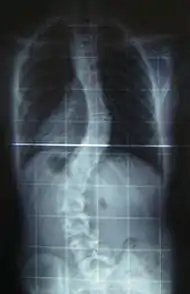

The prognosis of this sub-type of MD indicates that the affected individual may eventually have feeding difficulties. Surgery, at some point, might be an option for scoliosis.[3]

Scoliosis, which is a sideways curve of the persons vertebrate, is determined by a variety of factors, including the degree (mild or severe), in which case if possible a brace might be used by the individual.[12]